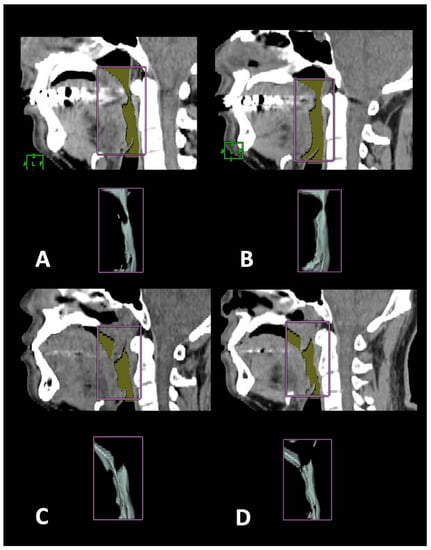

2.5. Surgical Plan and Design for Coblation Whole Tongue Surgery